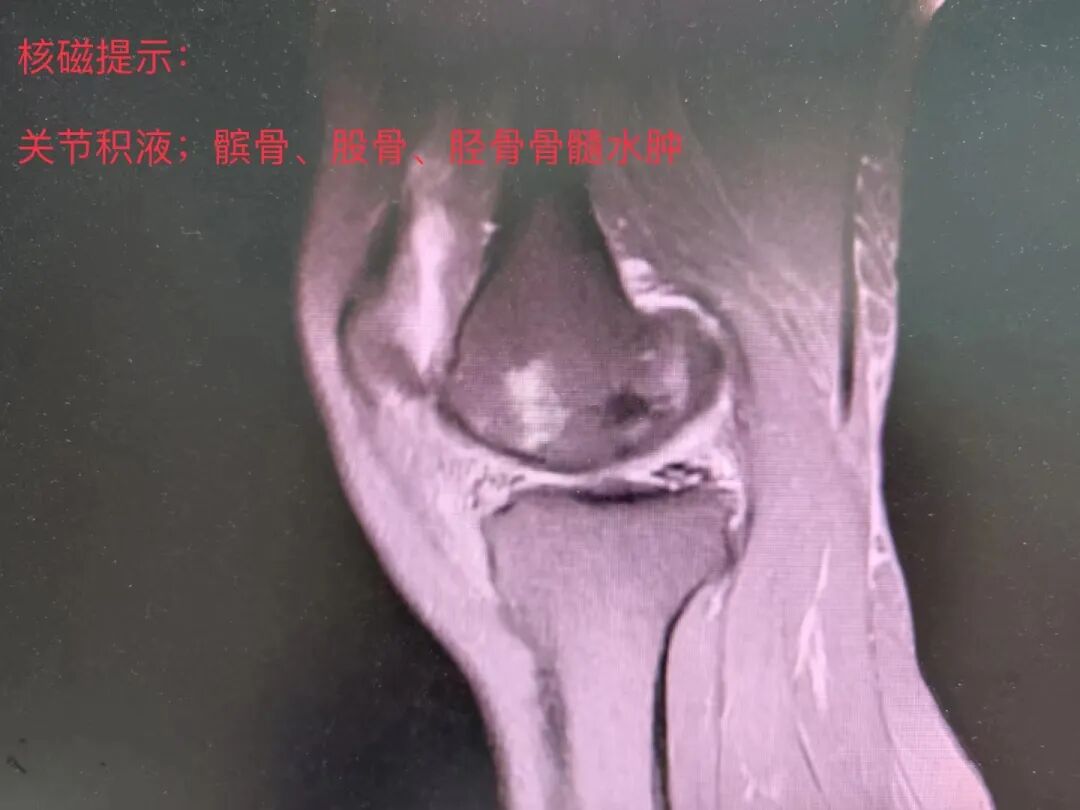

家人紧急之下把吴女士带到就近医院看诊,在注射玻璃酸钠,口服营养软骨药物治疗后,症状无明显改善。为求进一步专科治疗,2022年10月27日转来我院继续治疗。

关节科主任邓群波了解到:吴女士一年前已经出现了这个右膝关节疼痛,尤其是跳广场舞或者下蹲做家务后,疼痛会加重。但她瞒着家人,自己到药店购买了止痛药物,最近这两个月止痛药物已经没有什么效果了,走路都受到了影响。于是安排了患者住院进行进一步详细检查。

结合患者病史、查体及影像学资料,经科内会诊后决定给吴女士行人工单髁关节置换术,术中所见: